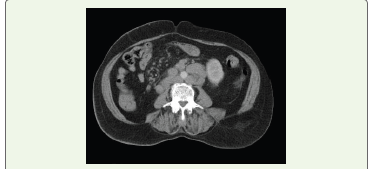

Figure 1:Axial section of CECT abdomen in portal venous phase showing

multiple enlarged homogenous pre-aortic, para-aortic and aortocaval,

perivcaval and retrocaval nodes.